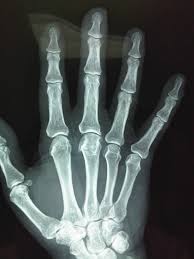

Bienvenidos a Imedicas Diagnósticas |

IMEDICAS DIAGNOSTICAS EU, es una Institución dedicada a la prestación de servicios de apoyo diagnóstico en radiología al sector de la salud, contando con una amplia experiencia, con personal calificado y entrenado para ofrecer el mejor servicio que usted requiere.

Nuestros Servicios: RX de Torax, RX de Columna, RX de Miembros superiores e Inferiores

Los Rayos x simples ambulatorios no requieren de preparación ni cita previa |